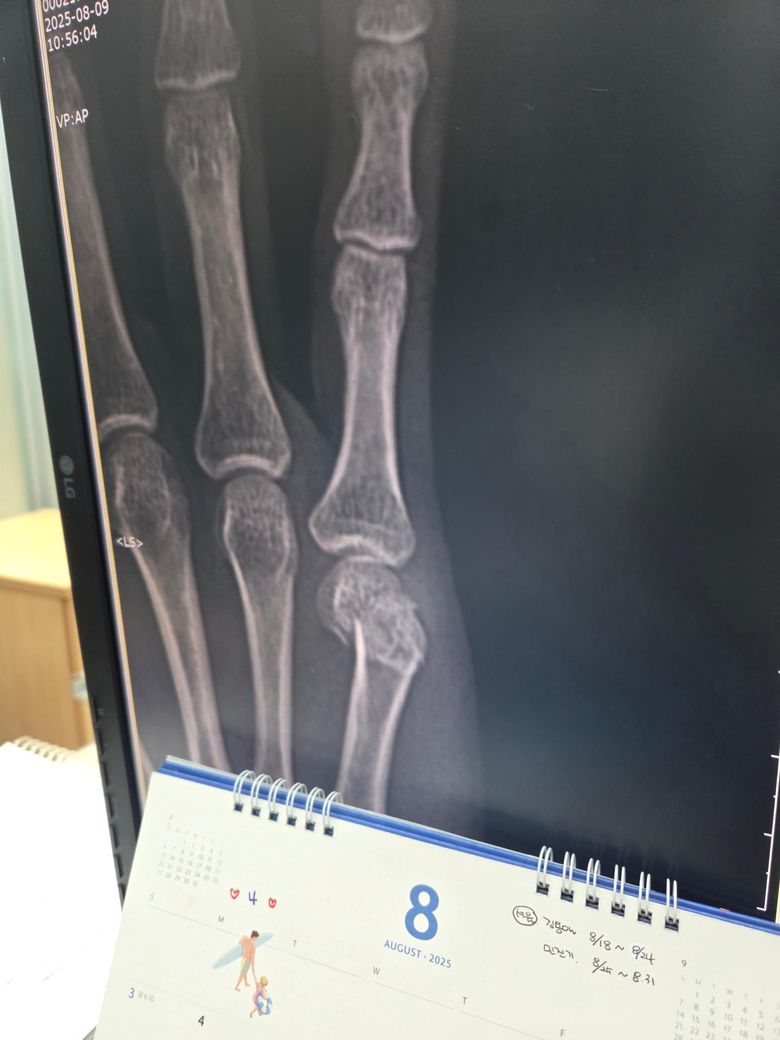

중수골골절 수술 한 번만 봐주세요 사진 있어요

중수구 이 골절되어 있습니다

사진 한 번 봐주시고 꼭 수술을 해야 될 정도로 큰 골절인가요? 깁스만으로는 어떻게 안될까요 수술하려는데 무서워서 병원도 한 군데 갔어요

올려주신 엑스레이를 보면 중수골 골절이 확실하며 골절 부위가 심하게 어긋나 있고 분쇄된 모습도 일부 보입니다.

이 정도 전위와 변형이 있으면 깁스 단독 치료보다는 수술로 뼈를 정확히 맞추고 고정 하는 것이 기능 회복에 유리합니다. 수술을 통해 손가락 변형, 관절 강직, 만성 통증 등의 후유증 위험을 줄일 수 있습니다. 병원 한 곳만 믿기 어렵다면 정형외과 전문의 2곳 이상 상담을 받아보는 것도 추천드립니다!

골 절편이 어긋나있는 양상이 있습니다.

정렬 자체가 올바르다면, 보존적 처치가 가능할 수 있으나, 질문자분 경우에는 수술 요할 수 있을것 같습니다. 보다 자세한 사항은 정형외과 전문의와 상의하시는것이 가장 정확해보입니다. 답변 도움되었기 바랍니다.